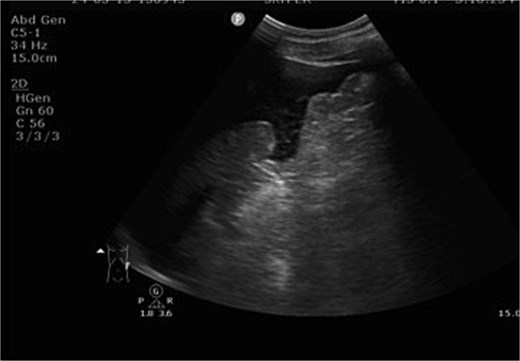

A 51-year-old male with a history of hypertension sustained multiple injuries in a high-speed motor vehicle accident. The patient was entrapped for approximately 30 minutes and presented to the emergency department with blunt abdominal trauma and an open fracture of the left tibia. On arrival, the patient was hypothermic (26.1°C), tachycardic (37 bpm), and initially normotensive (133/122 mmHg), with a Glasgow Coma Scale (GCS) score of E3V4M6. Primary survey revealed ecchymosis over the upper abdomen and left leg deformity. Focused abdominal sonography for trauma (FAST) demonstrated massive hemoperitoneum (Fig. 1). Despite initial resuscitation, the patient’s condition deteriorated rapidly within 10 minutes, with a drop in GCS to E1V1M4 and blood pressure to 70/55 mmHg, consistent with hypovolemic shock. Trauma red activation was initiated. Bedside sonography revealed rapidly increasing intra-abdominal free fluid. The patient experienced two episodes of pulseless electrical activity (PEA), both successfully resuscitated, and was transferred to the operating room within 15 minutes for emergency exploratory laparotomy.